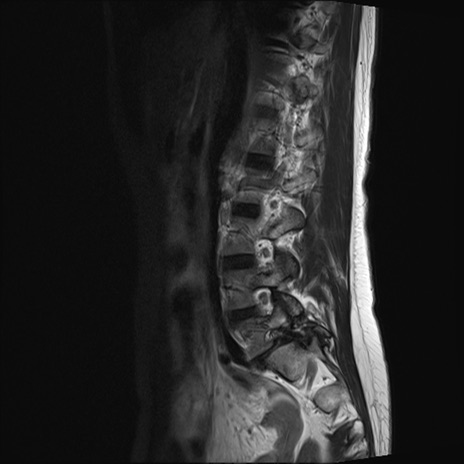

【整形】TIPS症例4 腰椎MRI T2WI(矢状断像)

腰椎MRI

STIR(矢状断像)